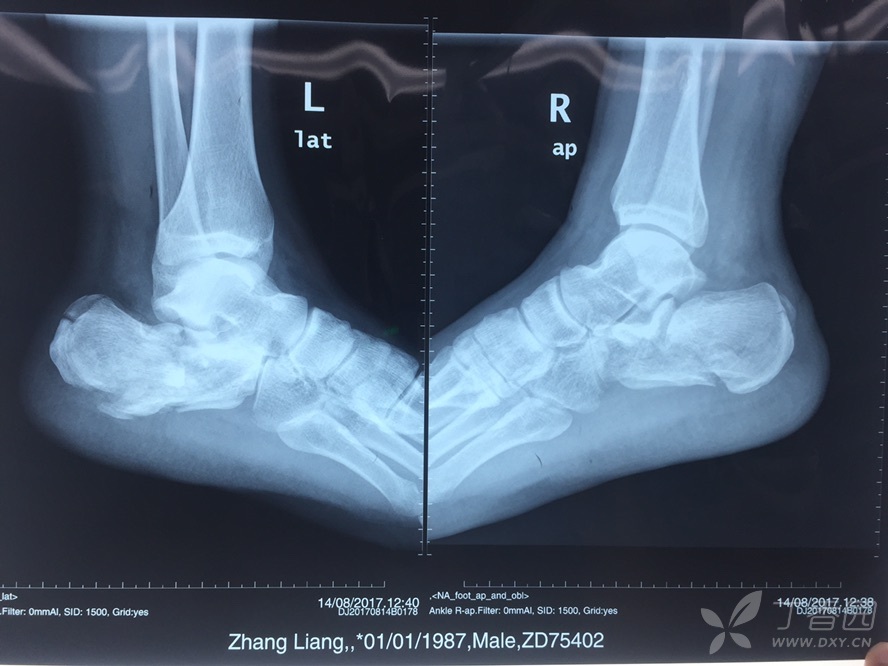

跟骨骨折 第一张是骨折当天拍的 第二张是

600x576 - 26KB - JPEG